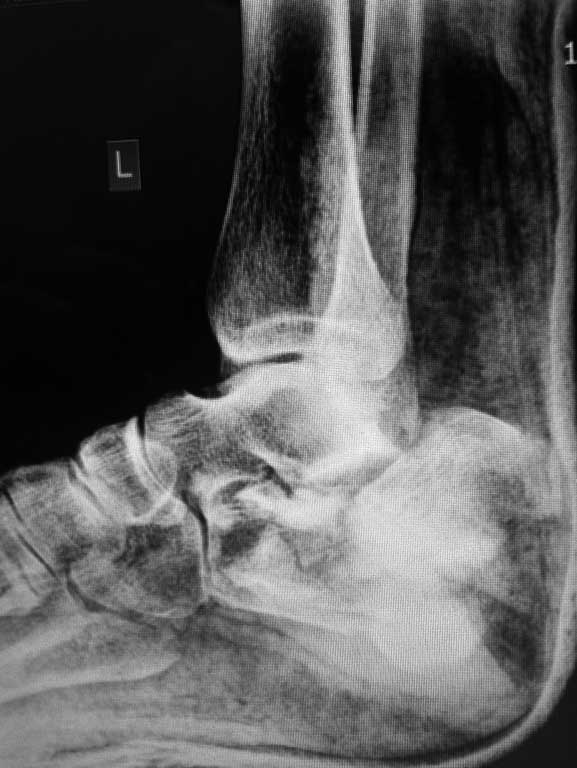

Даже на данном снимке можно . понять что перелом оскольчатый, внутрисуставной и захватывает заднюю и переднюю фасеты по крайней мере. Я тоже начал бы растягивать на аппарате (спицы спереди и сзади), но добавил бы locking plate открыто если больной кооперирующий и не курит. КТ нужна. Goodluck . Аарон

немного КТ